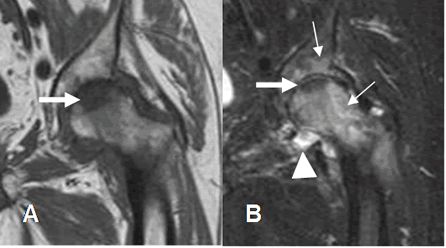

Fig 144 B. Artritis infecciosa.

A: RM coronal en T1 y B: RM coronal en STIR. Imágenes hipointensas en ambas secuencias, en la parte superior de la cabeza femoral, por osteonecrosis de evolución crónica. Pérdida del espacio articular, edema agudo en la cabeza femoral y cavidad articular (Flechas delgadas) y derrame articular. (Punta de flecha), por artritis infecciosa.